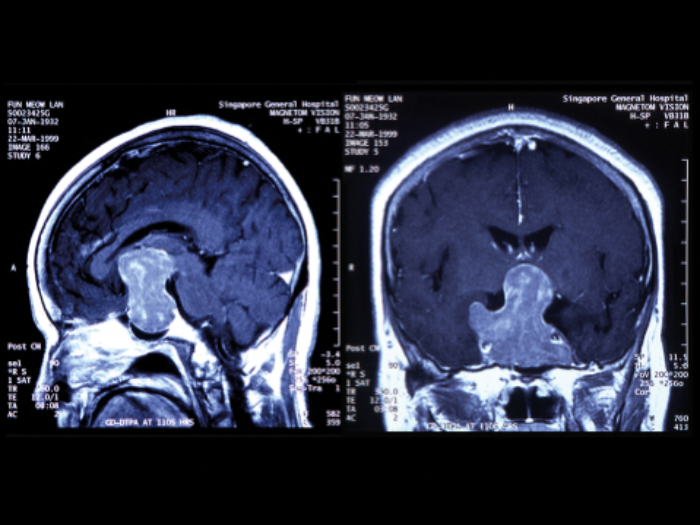

Figure 3: MRI scans showing a large pituitary tumour with (left) saggital image

showing upward extension and (right) coronal image, showing invasion of both cavernous sinuses.

If untreated a pituitary tumour will continue to expand slowly over months or years, most commonly upwards (Figure 3, left) causing further compression of the visual pathway and eventually blindness. Lateral spread is into the cavernous sinus (Figure 3, right) when an ocularmotor palsy, usually the sixth, will develop. Once the cavernous sinus is invaded, a tumour in this area cannot be safely removed. Rarely a tumour can extend even further into the temporal or parietal lobe of the brain (Figure 4).